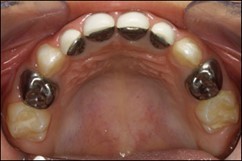

Prefabricated crowns

Prefabricated crowns have been widely used in paediatric dentistry for 50 years.